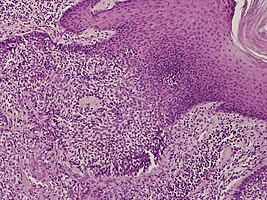

Dermoscopy and histopathology of eccrine poroma: (A) Clinical presentation of a nonpigmented eccrine poroma sensu stricto as a pink nodule located on the foot (B,C) Dermoscopy shows milky red areas (light blue arrow), milky red globules (dark blue triangle), and dotted vessels (black arrow) (original magnifications ×20 and ×40, respectively). (D,E) Histopathologically, the neoplasm consists of poroid and cuticular cells and tubular structures that are continuous with the epidermis (H&E stain, original magnifications ×10 and ×40, respectively).[6]

They are described as < 1 to 2 cm, pink/red shiny, exophytic lesions that can be pigmented and are clinically very similar to pyogenic granulomas.[3] Histologically, the cells as PAS-positive and clearly surrounded by normal keratinocytes. These tumors are surgically excised usually without complication or recurrence, although malignant porocarcinomas can recur and metastasize to local lymph nodes.[5]